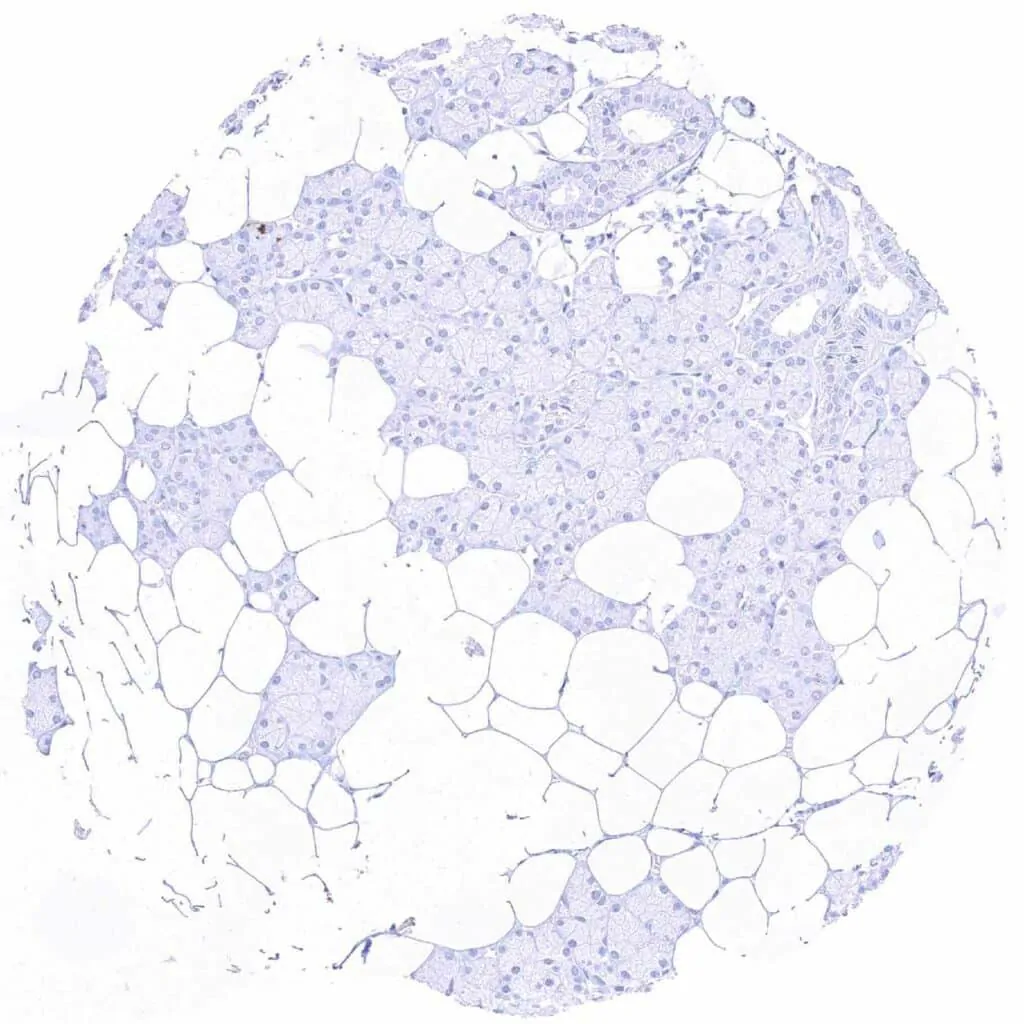

Liver